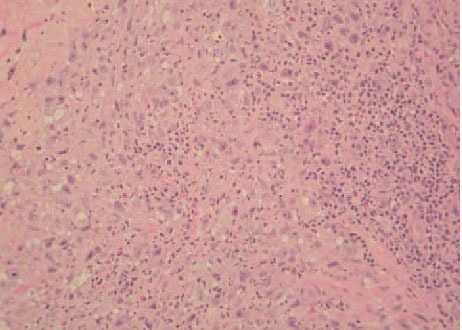

Una mujer de 73 años, diagnosticada de enfermedad de Hodgkin en estadio IV-E, de tipo depleción linfocitaria, presentaba una lesión osteolítica en el ala sacra izquierda que englobaba partes blandas y raíces nerviosas y otra masa en la quinta vértebra lumbar. La paciente consultó por la presencia, en la misma región lumbosacra izquierda, de unas placas eritematosas, de 1-2 cm de diámetro, muy infiltradas a la palpación y de tiempo de evolución indeterminado (fig. 1). Se practicó una biopsia cutánea, en la que se pudo observar un infiltrado tumoral que afectaba a la dermis profunda y al tejido celular subcutáneo, respetando la dermis superficial y la epidermis. La neoplasia estaba constituida por abundantes células mononucleadas atípicas (células de Hodgkin) y por células multinucleadas correspondientes a células de Reed-Sternberg (fig. 2), acompañadas por un escaso infiltrado de células inflamatorias no neoplásicas compuesto por linfocitos, eosinófilos e histiocitos predominantemente, en una estroma desmoplásica (fig. 3). Las células neoplásicas fueron positivas para CD30, CD15 y aisladas células se tiñeron con antígeno de membrana epitelial (EMA). No se obtuvo inmunotinción positiva para el antígeno leucocitario común (CD45), para marcadores B (CD20 y CD79a), marcadores T (CD3, CD43, CD4 y CD8), ni para el resto de anticuerpos monoclonales empleados (creatincinasa, HMB-45, CD68, CD21 y ALK).

Fig. 2.Célula de Reed-Sternberg (flecha continua) y célula de Hodgkin (flecha discontinua). (Hematoxilina-eosina, ×100.)